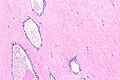

Microscopic

Features:

- Hyaline material.

- Loss of glands.

Prostate gland